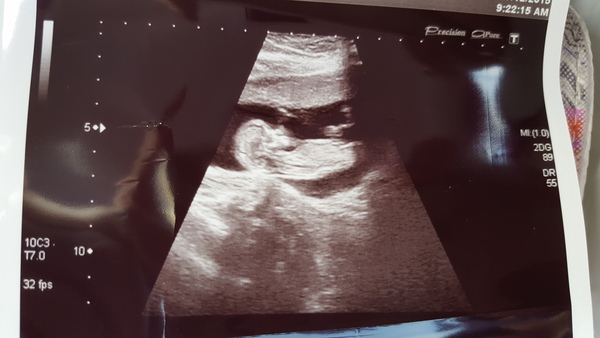

So we have ONE little wriggler who didn't want to be measured this morning but we got there in the end! Plus dr has put my meds on repeat - bonus!

Awww iam a lovely scan picture! mmminx I'm a teacher too, don't be guilt tripped into going to work if you're not well enough... Push for another sick note!

Iam congrats on the scan.

Lovely to see your scan photo Iam. Smile